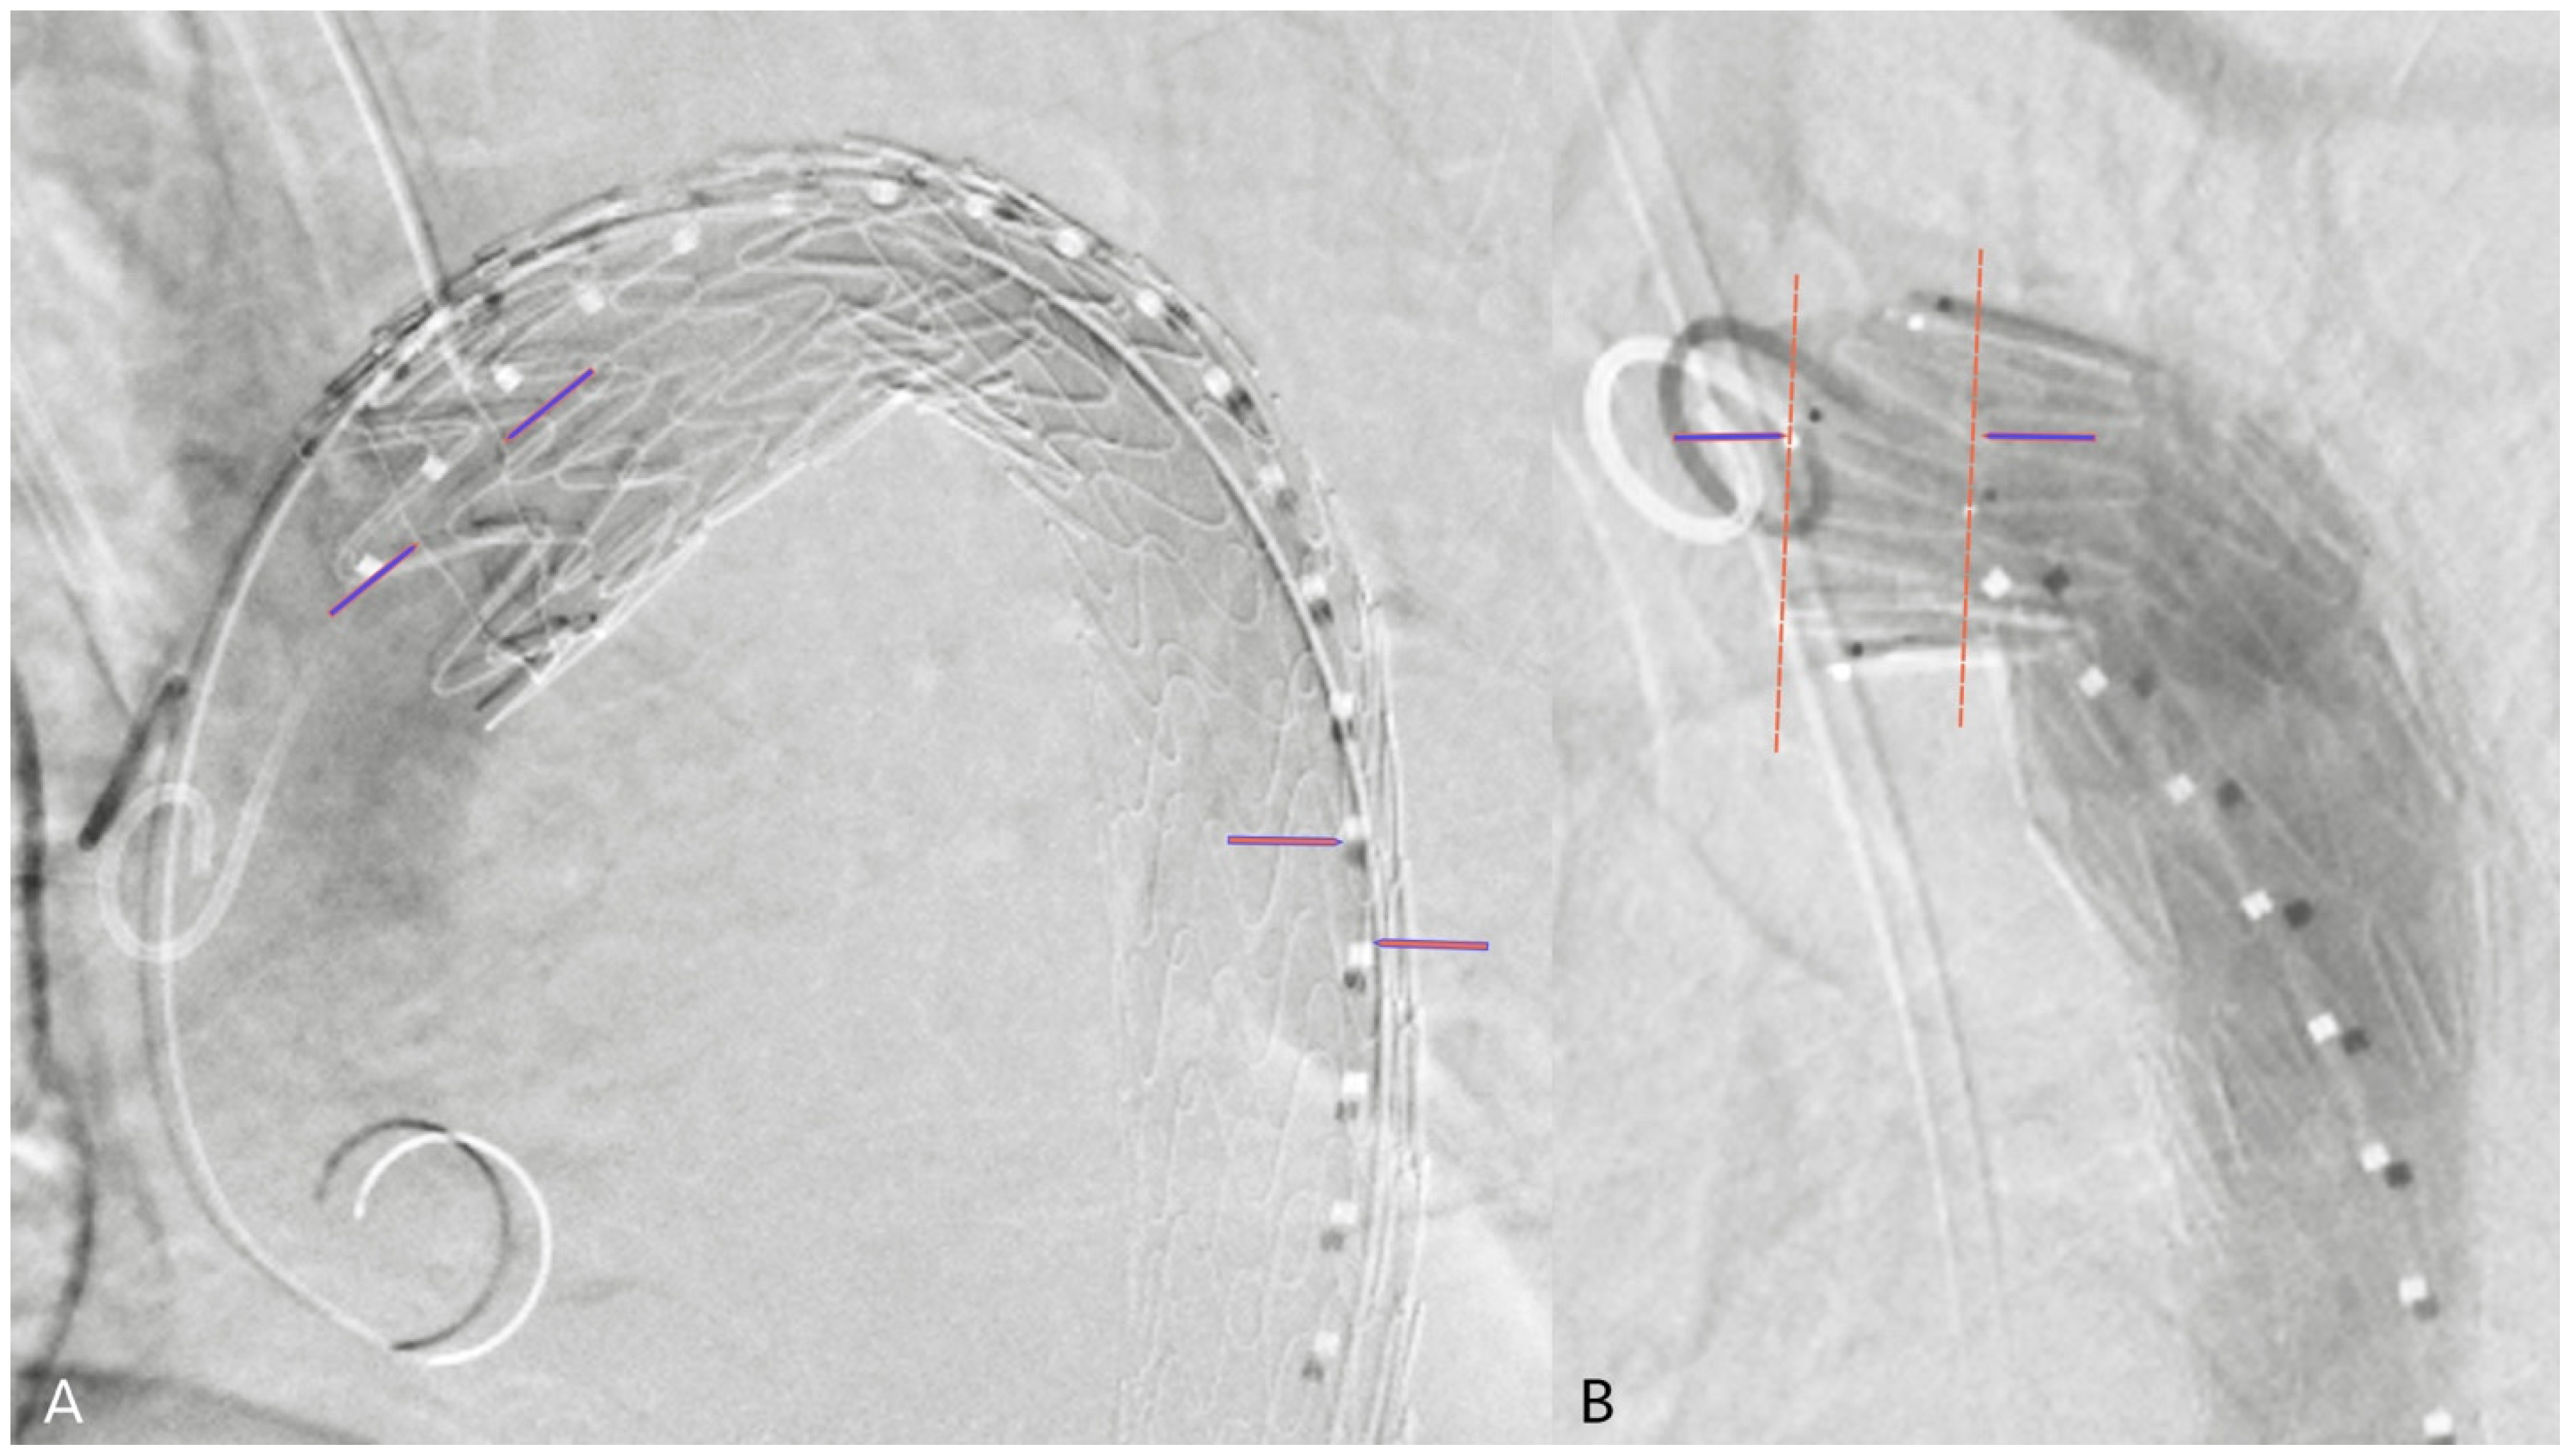

2.4. 2D3D Fusion Technique

2.5. 3D3D Fusion Technique